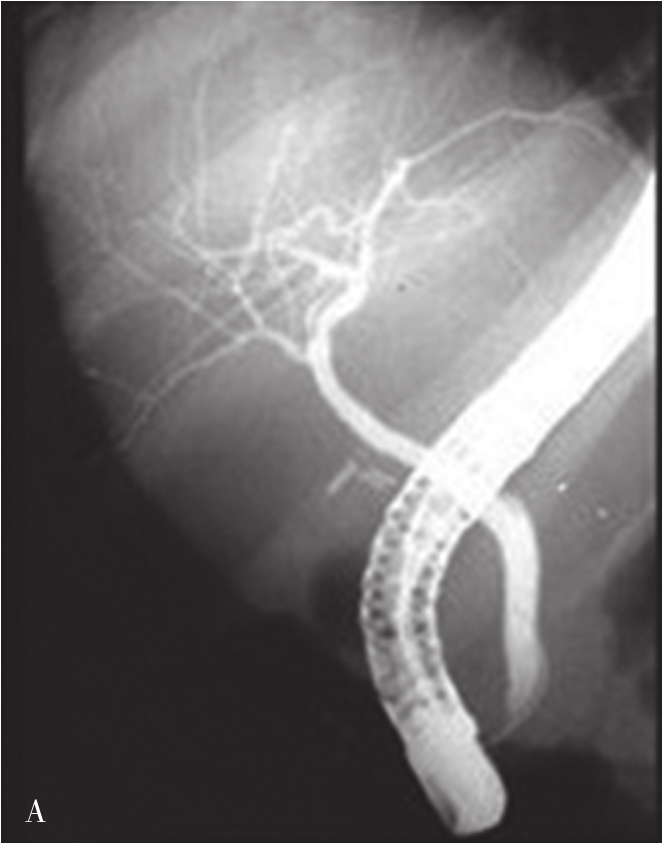

内镜逆行胰胆管造影(endoscopic retrograde cholangiopancreatography,ERCP)指将十二指肠镜插至十二指肠降部,找到十二指肠乳头,由活检管道内插入造影导管至乳头开口部,注入造影剂后进行X线透视和摄片,以显示胰胆管的技术。临床上是显示胰胆管的主要方法之一。它使成像的胆管系统可达到最大可能的范围,若插管成功,注入造影剂,可见内镜逆行胰胆管造影(图5-21-45)。同时可以进行各种治疗程序。如胆总管结石的诊疗中,以往需要外科手术治疗,存在手术创伤大、术后恢复慢、结石残余或复发等难题。在采用ERCP后只需通过十二指肠乳头小切口,即可对肝外胆管结石(图5-21-46)进行碎石、取石、清理等操作。ERCP最早的报道在1968年,随着器械和技术的进步,而在临床上得到推广应用。目前,临床上应用ERCP并不是单纯为了诊断胆管系统的疾病,因为已有了更微创和有效的手段,如磁共振胰胆管成像(magnetic resonance cholangiopancreatography,MRCP)和超声内镜(endoscopic ultrasound,EUS),而主要应用在处理胆道的疾病。适应证主要有胆道梗阻引起的黄疸,如急性胆管炎、胆总管结石、胆道狭窄、胆漏、胆道出血和Oddi括约肌功能紊乱等。内脏穿孔为绝对禁忌证,凝血功能异常、无并发症的急性胰腺炎和心肌梗死都是相对禁忌证。以下简述其技术方法:

图5-21-45 内镜逆行胰胆管造影法示胰胆管

可见胆囊及胆系树枝状影像,并清晰显示胰管走行

ERCP采用有侧视(side-viewing)的十二指肠镜,经口送入十二指肠后,通过灯光观察到十二指肠乳头,并且可以侧视孔插管进入胆总管内。操作需要在透视下完成。胆管插管成功后,可以注入造影剂显示肝内外胆管(图5-21-47)。正常胆总管直径小于6mm。胆囊切除术后和年龄大于70岁者,胆管直径可能达到9~10mm。也可以引入导丝和其他器械,以进行诊断和治疗。应用括约肌切开器切开十二指肠乳头,有利于其他器械引入到胆管内。

有经验的内镜医生ERCP的成功率可达90%~95%,行Billroth Ⅱ胃肠吻合术后,技术成功率可下降到60%。ERCP不成功的患者,可以选择经皮肝穿刺胆道造影。ERCP也是一种有创的手段,且可发生并发症,最常见是急性胰腺炎,发生率为2%~5%。另外,还可能有出血或穿孔等,发生率均低于1%。